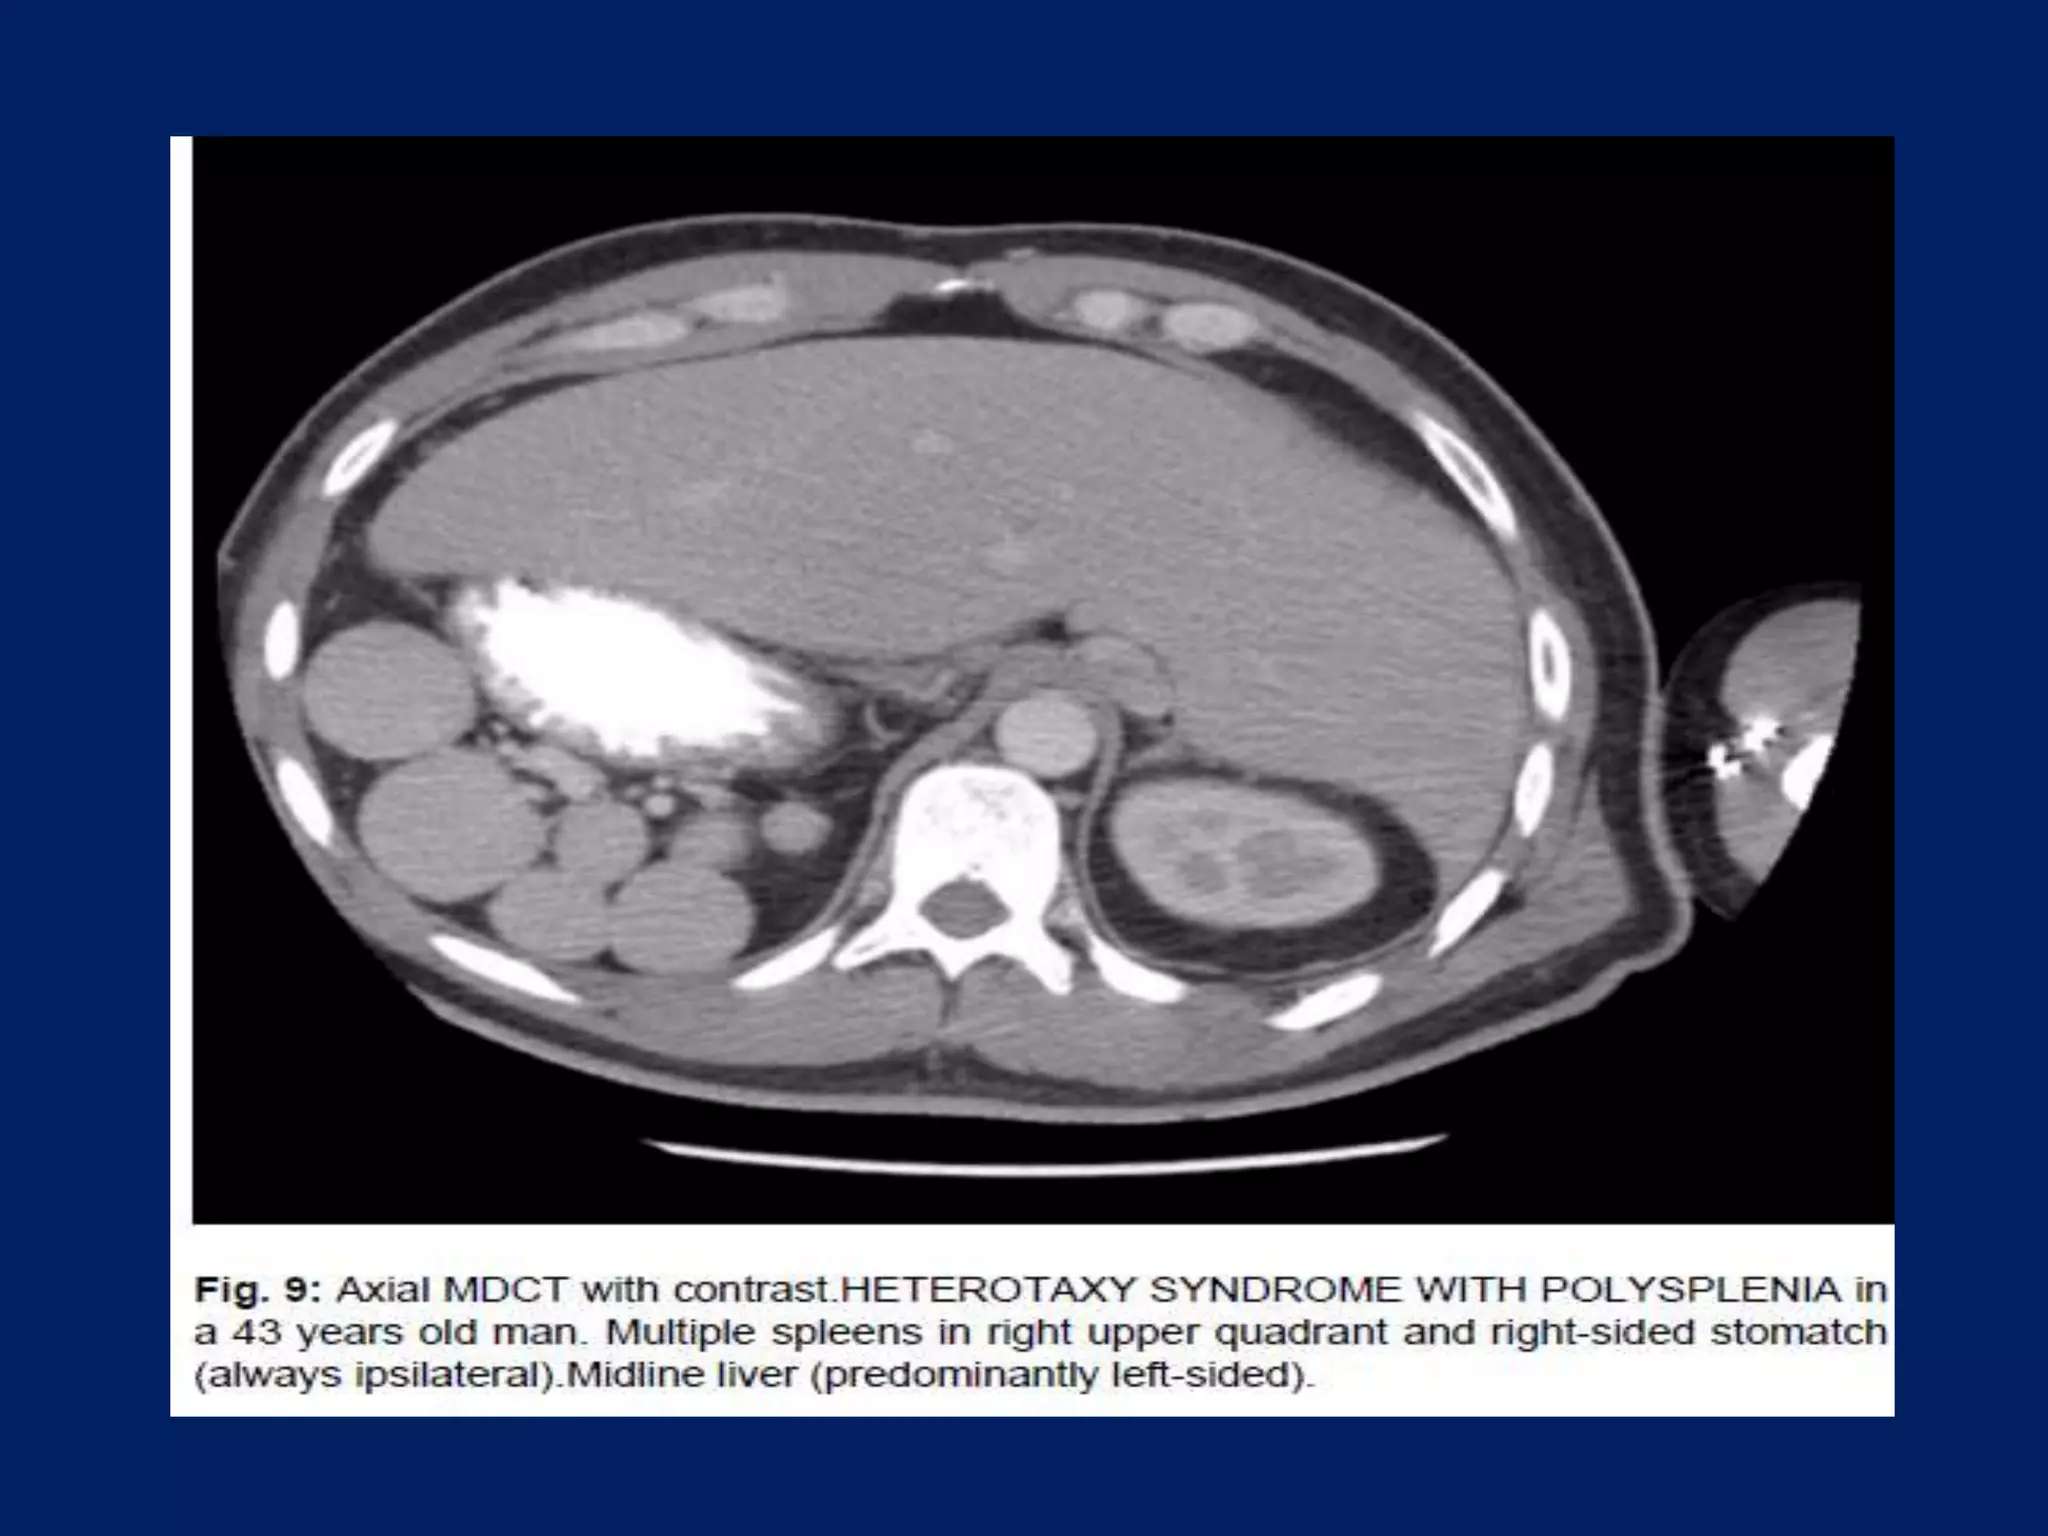

This document discusses imaging of the spleen and summarizes various congenital anomalies and pathologies that can affect the spleen. Some common congenital anomalies mentioned include accessory spleens, asplenia, polysplenia, and splenic fusions. Acquired conditions like repeated infarctions, infiltration, tumors, and cysts can also cause splenomegaly or functional asplenia. Wandering spleen is discussed as a rare congenital anomaly where the spleen lacks attachments and is mobile within the abdomen. Various grades of splenic lacerations and examples of splenic imaging findings are also briefly summarized.